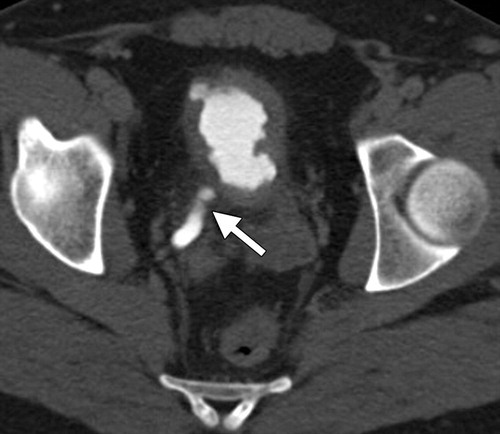

SPOTTED NEPHROGRAM

Figure 5A

A late arterial phase from an aorto- gram shows bilateral spotted neph- rognams in a patient with polyartenitis nodosa.